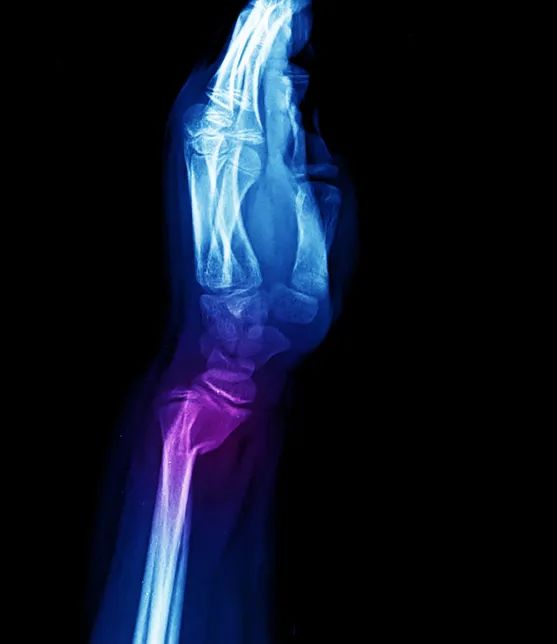

典型畸形姿态即侧面看呈「银叉」畸形,正面看呈「枪刺样」畸形。X 线可见骨折远端向桡、背侧移位,近端向掌侧移位。

受伤后腕部下垂,局部肿胀,腕背侧皮下瘀斑。X 线可见典型移位,近折端向背侧移位,远折端向掌侧、桡侧移位。可合并下尺桡关节损伤、尺骨茎突骨折和三角纤维软骨损伤。

X 线拍片可发现典型的移位。当跌倒时, 腕关节屈曲、手背着地受伤, 可发生与上述相反的桡骨远端掌侧关节面骨折及腕骨向掌侧移位。